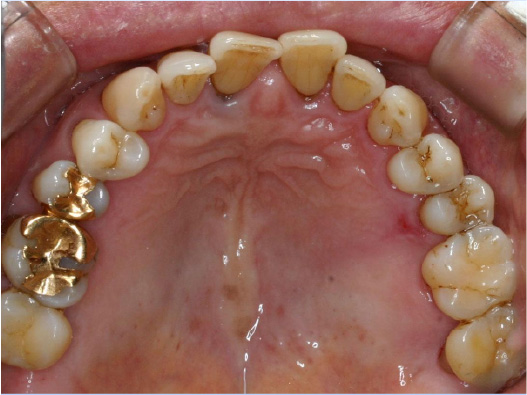

狭い歯列(狭窄歯列)によって、舌が歯列の中に収まらない状態です。

●高口蓋 ●低位舌 ●口呼吸

狭窄歯列(高口蓋)

右のように、狭窄歯列だと舌は、狭い歯列に阻まれて、前方や上方の口蓋に自由に動くことができません。その結果、舌は低い位置(低位舌)にあり、前方に出ず後方に位置するので、気道が狭くなってしまっています。

狭い歯列(狭窄歯列(きょうさくしれつ))

高口蓋(上顎が深い→鼻腔が狭い)

舌が歯列に納まらない→低位舌

歯並びが悪い

かみ合わせが悪い